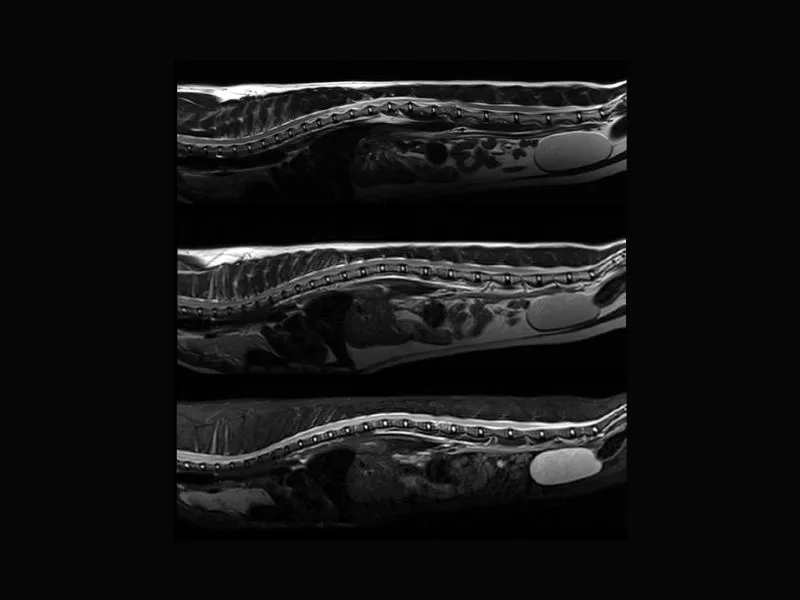

Supreme vet-mr – Multiple protruding discs in thoracolumbar, T1W and T2W slices